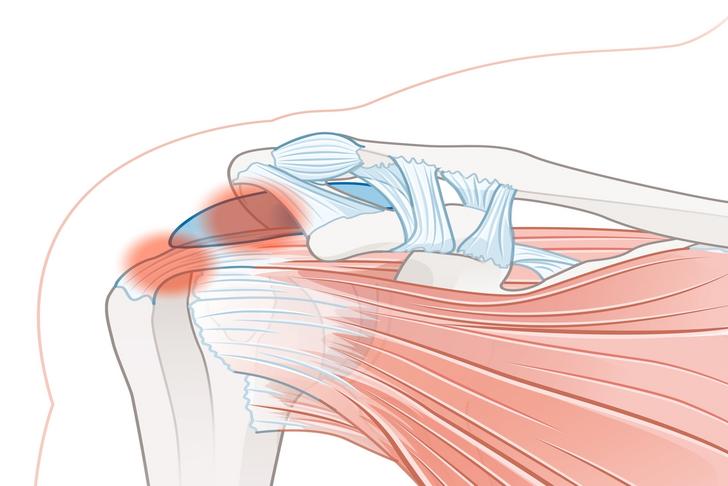

Shoulder Impingement

Shoulder impingement occurs when the rotator cuff tendons become compressed and irritated as they pass through the narrow space beneath the acromion, a bony projection on the shoulder blade [[4]]. This can lead to inflammation, pain, and limited range of motion in the shoulder.